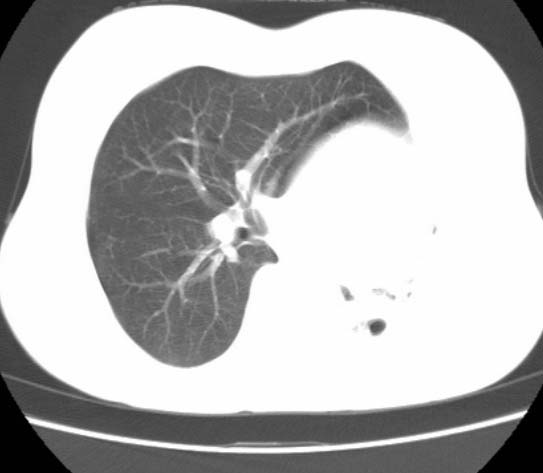

女  20岁。一月前咳血,诊“肺结核”抗痨治疗一月后,咳血停止,现复查。病人精神好。前后ct片对比未见明显变化。既往体检“正常”

1)考虑左肺结核并肺不张、支气管扩张。2)纵隔疝。

以前体检正常只能考虑左肺结核并肺不张、支气管扩张。2)纵隔疝。

考虑左肺结核,左肺毁损,纵膈左偏,既往体检正常不可靠,tb一个月也不会这个样子的,有钙化,应该病程较长,冰冻三尺非一日之寒!

左肺发育不全。

考虑左肺结核,左肺毁损,纵膈左偏,既往体检正常不可靠,tb一个月也不会这个样子的,有钙化,应该病程较长,冰冻三尺非一日之寒